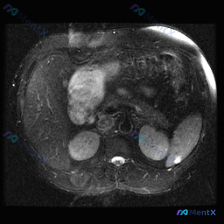

用户明确问的是「脾脏病变」,提供的是一张腹部MRI-T2加权轴位图像。

👉 在这张图像上,脾脏实质信号均匀,皮髓质分界清晰,没有看到局灶性的高信号或低信号占位,也没有结构破坏。 单从这张图看,脾脏没有发现明确病变。

图像里肝脏的表现非常抢眼:

- 肝脏右叶(及散在其他部位)可见多发类圆形结节;

- 信号特征:呈均一的显著高信号(T2高亮),亮度接近于胃液这种纯液体信号;

- 边界:非常锐利、清晰,没有周围组织浸润或明显受压变形。

从T2信号看,这是典型的「灯泡征」,鉴别方向很明确:

- 肝海绵状血管瘤(最可能):支持点是多发、边界清、T2信号极高(灯泡征),这是最常见的肝脏良性占位之一,概率>90%;

- 肝囊肿(待排):也可以表现为T2高信号、边界清,但通常血管瘤的T2信号会更「亮」一点,而且多发血管瘤比多发单纯囊肿更常见一些。当然,单靠这张T2平扫没法100%区分两者。